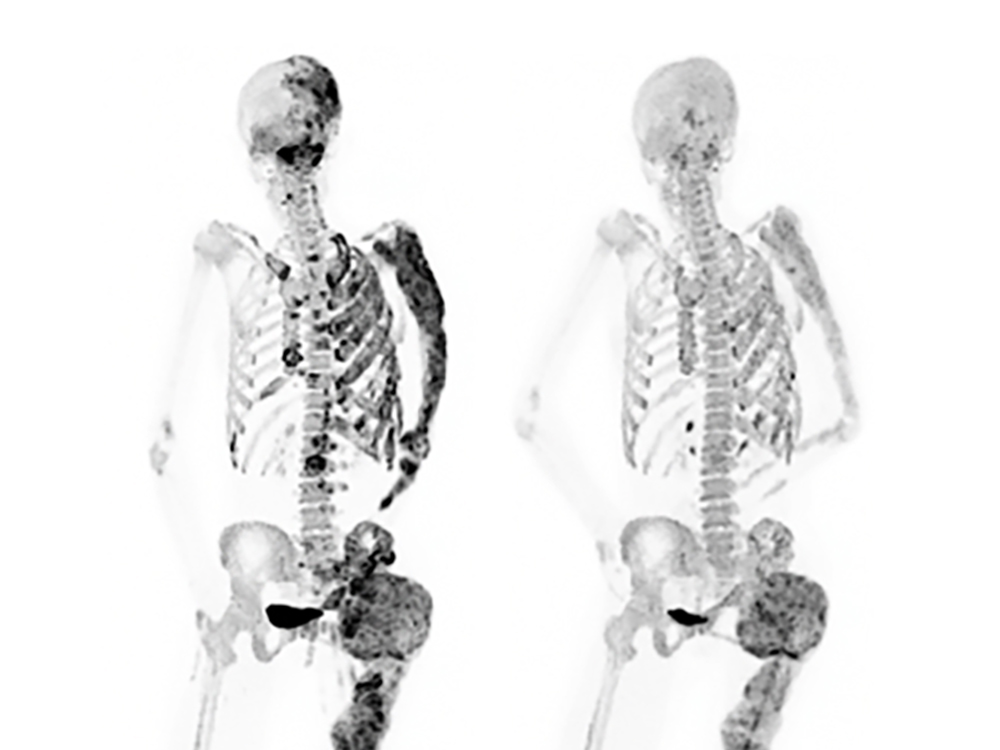

Ido Simyoni, a man from New York, underwent surgery to remove multiple tumors in his forehead caused by fibrous dysplasia, a condition that causes scar-like tissue to form instead of normal bone. The surgery left him with a large dent in his forehead, but he is grateful to be alive. Ido had been living with the condition since he was 15 years old and had previously undergone surgery at 17 to remove a tumor near his brain. After experiencing swelling last year, he underwent two more surgeries to remove a tumor and replace his forehead bone. Despite the challenges, Ido is now on the mend and plans to run all six World Major Marathons in 2024.